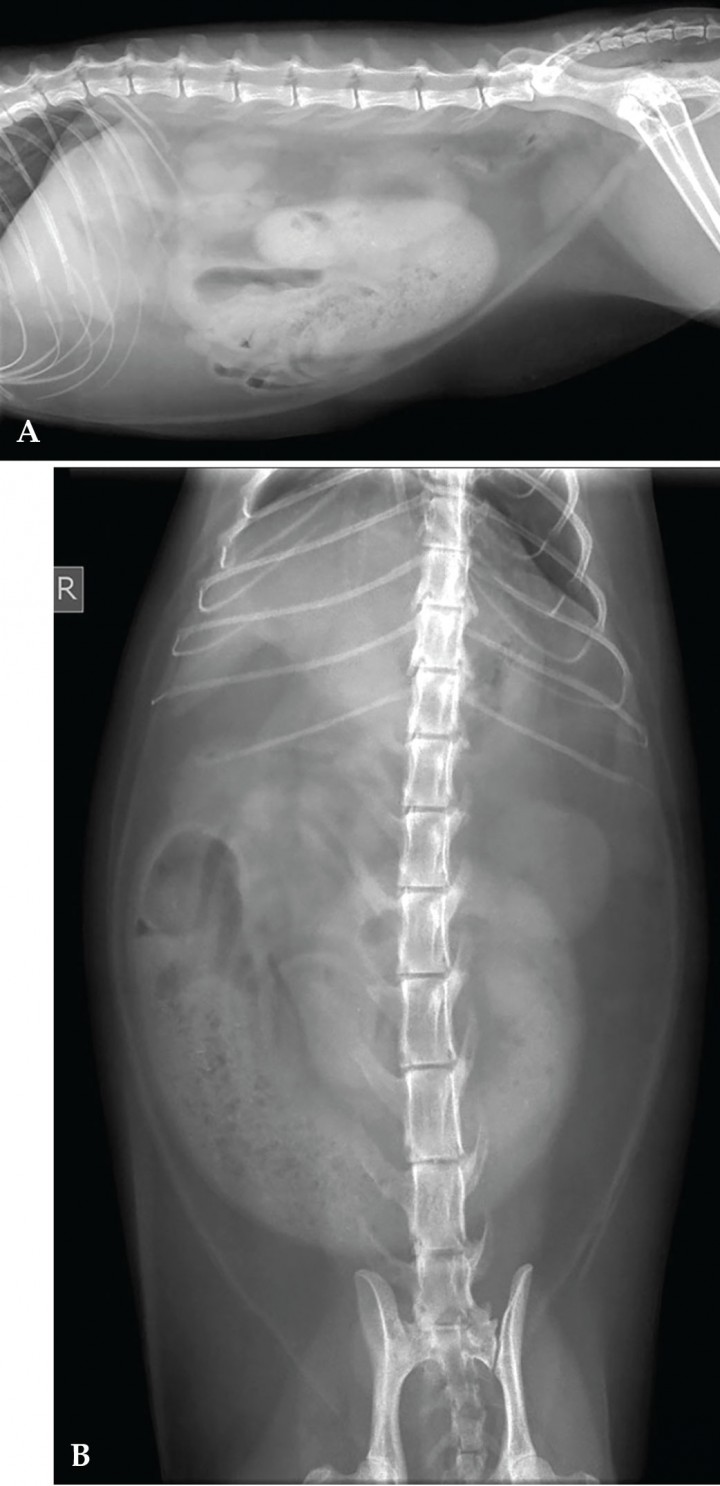

Se presenta una gata Común Europeo, castrada, de 6 años de edad y 3 kg de peso con un cuadro de anorexia, constipación, vómitos fecaloides y pérdida de peso de 15 días de evolución. No está vacunada, pero sí desparasitada, y es negativa a inmunodeficiencia felina (FIV) y leucemia felina (FeLV). A la palpación abdominal se aprecia una masa en abdomen medio derecho. El hemograma y la bioquímica sérica revelan leucocitosis e hipoalbuminemia. Se realizan radiografías de abdomen en proyecciones lateral derecha y ventrodorsal (Fig. 1).

<p>Radiografías de la cavidad abdominal de una gata Común Europea de 6 años. (<strong>A</strong>) Radiografía lateral derecha. (<strong>B</strong>) Radiografía ventrodorsal. R: derecha.</p>

Radiografías de la cavidad abdominal de una gata Común Europea de 6 años. (A) Radiografía lateral derecha. (B) Radiografía ventrodorsal. R: derecha.